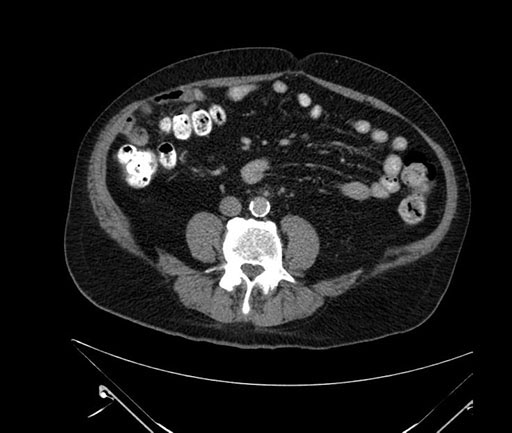

Imaging Analysis

Look through the patient's CT scan to identify any areas of concern for the necessary procedure.

Based on your CT findings, which issue(s) would give reason for "planned slowing down moment(s)" in this case?

Considering a standard Whipple procedure, what step(s) of the operation would you do differently in this case?